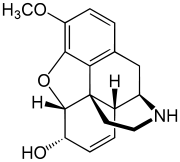

Structures

| Morphides | ||||

|---|---|---|---|---|

Codeine Codeine |

Morphine Morphine |

Oripavine Oripavine |

Pseudomorphine Pseudomorphine |

Thebaine Thebaine |